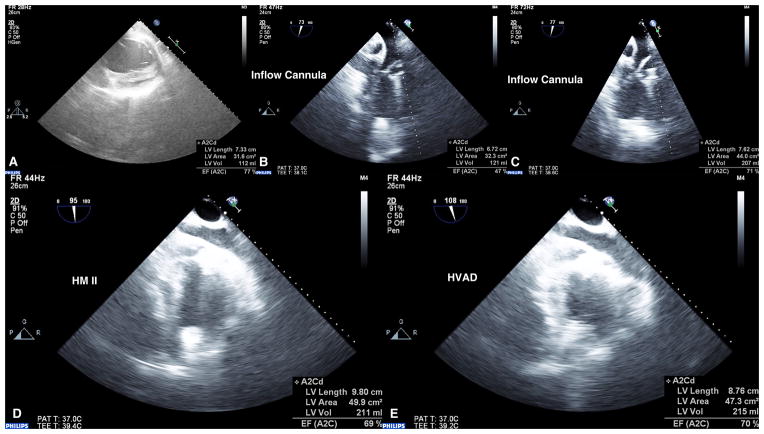

Figure 8.

Echocardiography images (3D iE33 Phillips Medical Systems) recorded at pre-implant baseline (A), post-implant of SBH connector system with HeartWare HVAD operating at maximum pump speed (B) and normal pump speed with animal in acute hypertension (C). Images of Thoratec HeartMate II (D) and HeartWare HVAD (E) LVAD with SBH connector system demonstrating hemostasis was maintained and LV volume unloading achieved.

Echocardiography (weekly evaluation) and fluoroscopy (implant and explant evaluation) verified the in vivo position of the SBH connector system and LVAD system over 30-day study period. On day 30, LV and arterial pressures demonstrated hemostatic seal was maintained as evidenced by LV and arterial pressures over a range of LVAD support and during simulated hypertension (Figure 9). There were no arrhythmias observed and ventricular function (% EF) was preserved (Animal 1: 77% Implant, 71% sacrifice; Animal 2: 73% implant, 72% sacrifice). There were no device failures and both calves completed the 30-day study. There were no significant changes in measurements of hepatic function (ALP, ALT) or renal function (creatinine) throughout the study period compared to baseline (Table 1), suggesting that the SBH connector system and LVAD did not negatively affect end organ function. Plasma free hemoglobin (pfHb), BUN, and creatinine levels were normal at all measured time points. All animals were electively sacrificed and a complete necropsy and histopathological analyses were performed on each animal, including examination of the SBH connector system and LVAD, all major abdominal and thoracic organs, and the brain. An independent pathologist (Mass Histology) examined all end-organ tissues and concluded that there were no notable histopathological changes when compared to other similar LVAD studies using calf models.